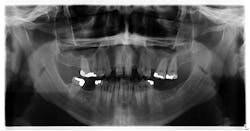

The patient's symptoms improved following the initial drainage; however, another flare-up commenced and it was recommended that a second biopsy be taken. Once the incision was made, a large void in the bone—approximately 2 cm in size—was noted (figure 4).

A large piece of the lower left posterior of the mandible was then resected and sent off for biopsy.